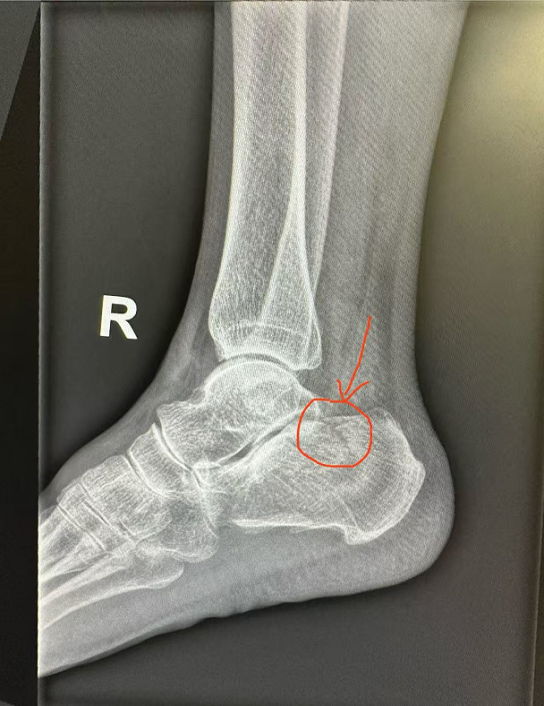

我的一位长辈,70岁。5个月前,右脚只是轻轻一崴,就导致了跟骨骨折(见下图)。“伤筋动骨一百天”,对她而言却远不止如此。历经了数月的固定、防血栓、补钙、康复,至今仍未完全恢复。最近的骨密度检查显示,她的T值低至-2.7。根据世界卫生组织标准,T值≤-2.5即可诊断为骨质疏松——她已明确进入这个“沉默的流行病”队列。

跟骨骨折